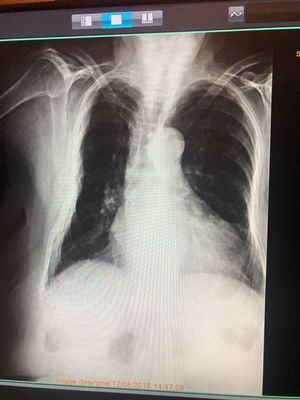

Pt complains of pain in right ribs, shortness of breath, and pain when standing

Lungs

Chest

Cxr